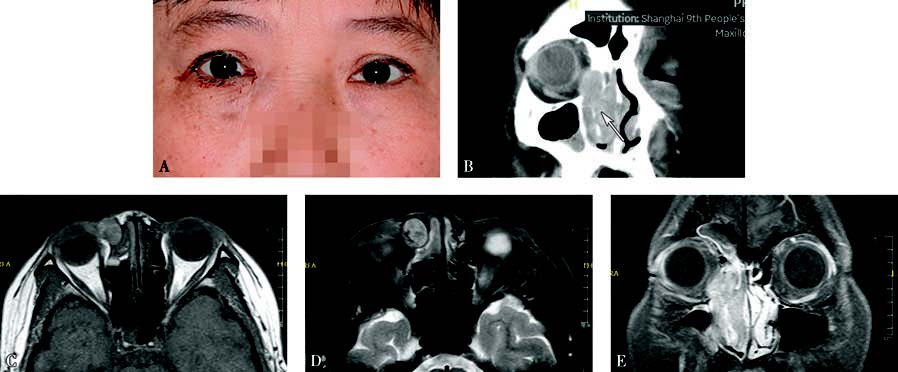

Figure 1 Appearance and imaging of a patient with right lacrimal sac melanoma

A. The patient presents with epiphora and bloody tears in the right eye. A black mass is visible at the lower lacrimal punctum, elevated above the lid margin, with a bulge in the medial canthal region.

B. Coronal CT shows an irregular mass in the lacrimal sac region, with destruction of the medial orbital wall and the nasolacrimal duct's bony structures, along with invasion into the ethmoid sinus and nasal cavity (white arrow).

C. Axial T1-weighted MRI demonstrates the tumor with intermediate to high signals.

D. Axial T2-weighted MRI shows the tumor with intermediate to low signals.

E. Coronal contrast-enhanced T1-weighted MRI reveals inhomogeneous enhancement of the mass.